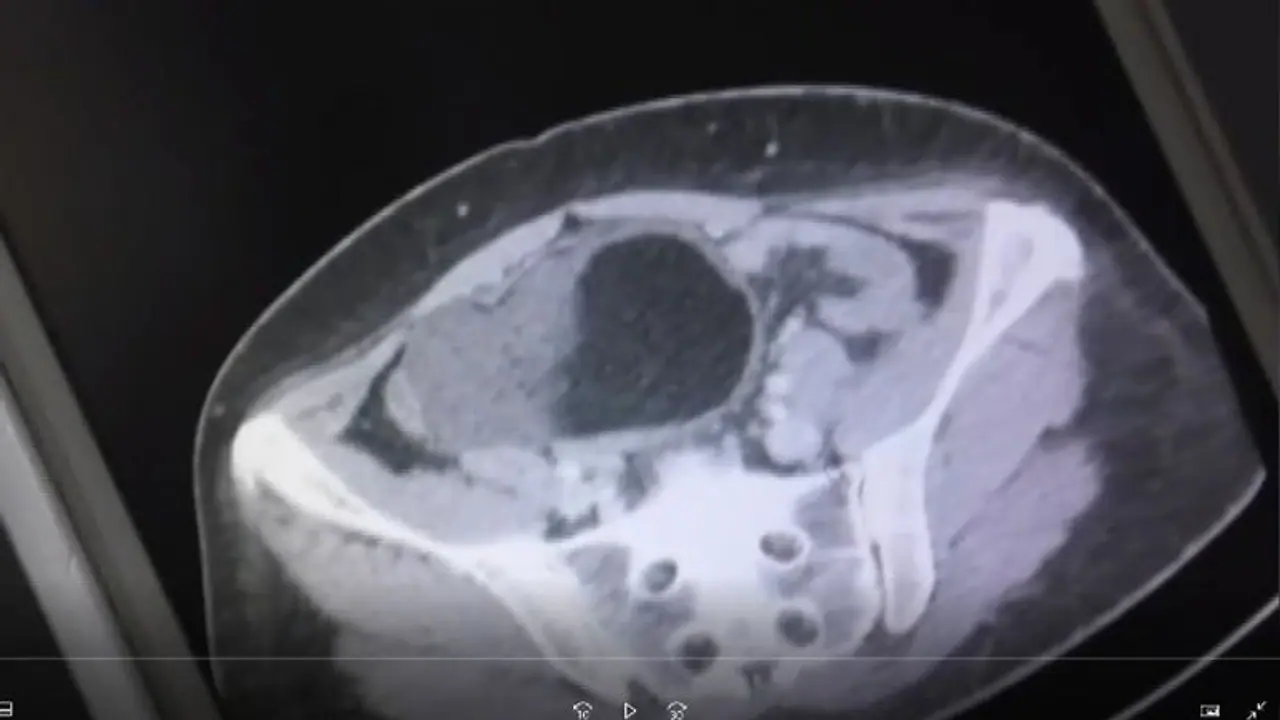

ബ്രിട്ടീഷ് വനിതയായ ഇമയ്ക്ക് ഉത്കണ്ഠയാണെന്നാണ് ഡോക്ടര്മാര് ആദ്യം പറഞ്ഞത്. ഇമയില് തെറ്റായ രോഗനിര്ണ്ണയം പല തവണ നടത്തി. ഒടുവില് നടത്തിയ പരിശോധനയിലാണ് ഇമയുടെ അണ്ഡാശയത്തനകത്ത് ഭീമാകാരിയായ ഒരു മുഴ വളരുന്നുണ്ടെന്ന് ഡോക്ടര്മാര് കണ്ടെത്തിയത്. ഒരു ഫുഡ് ബോളിന്റെ അത്രയും വലുപ്പത്തിലുളള മുഴയാണ് ഇമയുടെ വയറിനുളളില് ഉണ്ടായിരുന്നത്. വേദന കാരണം ഇമയ്ക്ക് ഭക്ഷണം പോലും കഴിക്കാന് പറ്റാത്ത അവസ്ഥയായിരുന്നു.

പ്രസവവേദനയെക്കാള് ഭീകരമായ അവസ്ഥയായിരുന്നും എന്നും ഇമ പറയുന്നു. വയറിന് കുറുകെ ചെറിയ വീക്കം തന്റെ ശ്രദ്ധയില്പ്പെട്ടിരുന്നു. വേദന ഒട്ടും സഹിക്കാന് പറ്റാത്ത സാഹചര്യമായപ്പോഴാണ് ഡോക്ടറെ കാണാന് തീരുമാനിച്ചതെന്നും ഇമ പറയുന്നു. തുടര്ന്നാണ് അണ്ഡാശയത്തനകത്ത് ഒരു മുഴ കണ്ടെത്തിയത്. കോശങ്ങള് ഉളള മുഴയായിരുന്നു അത്. ഭ്രൂണാവസ്ഥയിലുള്ളതായിരുന്നുവെന്ന് ഡോക്ടര്മാര് ഇമയെ അറിയിച്ചു. തുടര്ത്ത് ശസ്ത്രക്രിയയിലൂടെയാണ് ഇവ നീക്കം ചെയ്തത്.